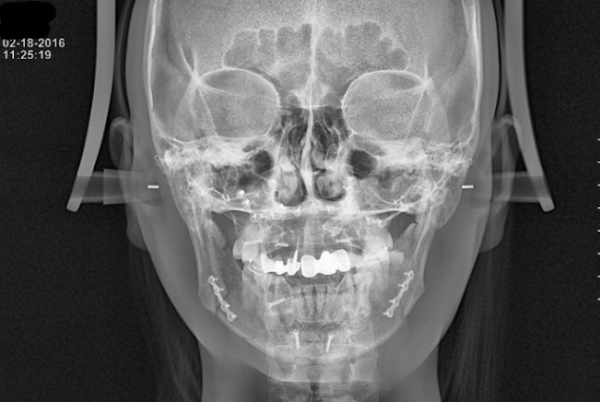

악(顎)교정술(턱의 위치나 모양을 변형시키는 수술)의 일종으로 윗턱인 상악(上顎)과 아랫턱인 하악(下顎)을 함께 수술하는 경우 양악(兩顎)수술이라 칭한다. 쉽게 말해 코 밑부터 아래턱 뼈 부분을 잘라내서 턱을 축소시켜, 얼굴을 바꾸는 치과 영역의 대수술.

양악수술을 하는 방법은 상악과 하악의 뼈를 잘라서 2개로 분리한 다음 정상 교합에 맞게 상악과 하악의 뼈를 이동시키고 이동된 뼈를 고정하는 방법이다. 뼈를 이동하는 대수술인 만큼 수술은 전신마취로 진행되며 보통 3일~7일 정도 입원하게 된다.

양악수술 한 사람의 엑스레이 상태